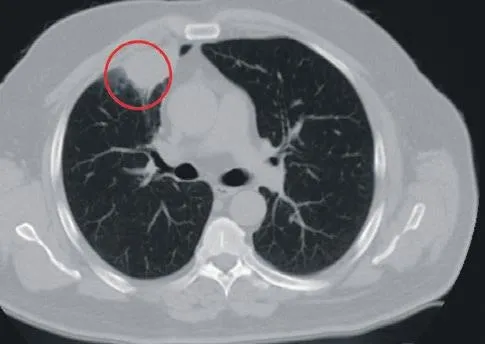

Kahramanmaraş Sütçü İmam Üniversitesi'ne göğüs ağrısı şikayetiyle gelen N.T.'ye tomografi çekildi. Sağ akciğerinde 4 santimetre çapında tümör tespit edildi. Kanser olabileceği şüphesiyle yapılan ileri tetkikler sonrası N. T.'ye akciğer kanseri teşhisi kondu ve acil ameliyat kararı verildi. Ameliyat öncesi hastanın Covid-19 testi pozitif çıkınca operasyon ertelendi. Koronavirüs tedavisine başlanan hastanın son testi negatif çıkınca ameliyat hazırlıklarına girişildi.

Kahramanmaraş Sütçü İmam Üniversitesi'ne göğüs ağrısı şikayetiyle gelen N.T.'ye tomografi çekildi. Sağ akciğerinde 4 santimetre çapında tümör tespit edildi. Kanser olabileceği şüphesiyle yapılan ileri tetkikler sonrası N. T.'ye akciğer kanseri teşhisi kondu ve acil ameliyat kararı verildi.